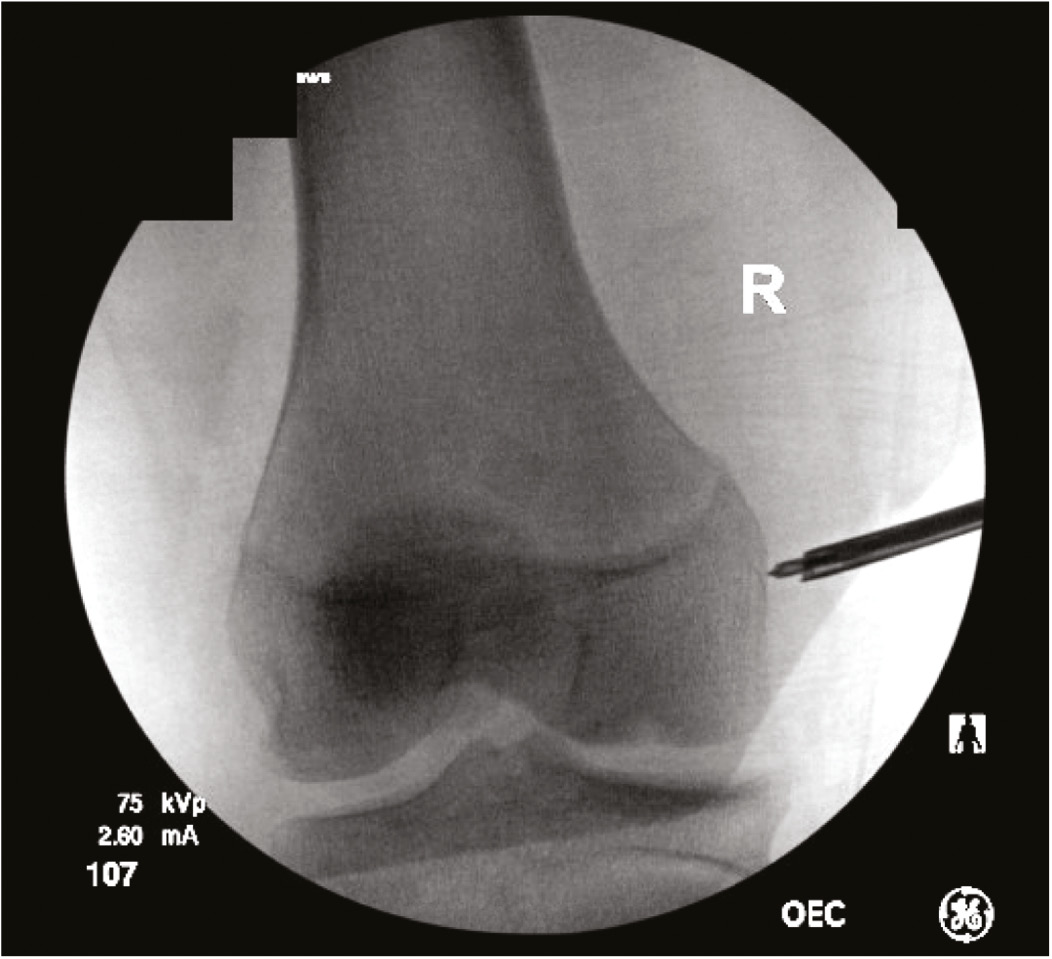

The authors preferred technique for MCL reconstruction in skeletally immature patients includes an all-epiphyseal femoral attachment at the origin of the sMCL near the medial epicondyle (Figure 11). Distally, spanning of the proximal tibial physis in order to attach the sMCL to its anatomic location is preferred (Figure 12). This distal attachment has been seen to be the primary stabilizer medially on cutting studies and therefore increases stability at the knee compared to staying all epiphyseal, which fails to reconstruct the distal limb of the sMCL.11 When the POL is also disrupted, such as in the setting of extensive multiligament knee injuries, MCL anatomic reconstruction with capsular imbrication (MARCI) technique is preferred to decrease tethering around the physis and due to a recent biomechanical analysis revealing better approximation of the intact state with imbrication in regards to valgus loading, internal and external rotation compared to the 4-tunnel anatomic reconstruction technique described by LaPrade.38

Figure 11. All-epiphyseal femoral attachment at sMCL proximal origin.

Figure 12. Distal sMCL insertion at proximal tibia.